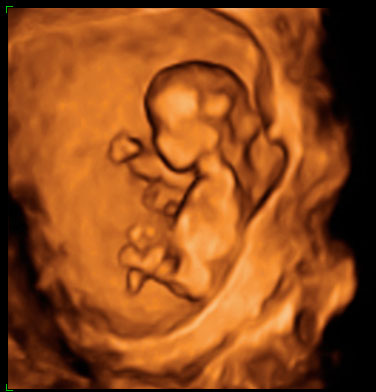

¿Qué aspecto tiene un embrión de 12 semanas?

El aspecto, sobre todo a partir de la semana 12, es parecido al de un recién nacido [ Ver ecografía en 3D ]. Se pueden distinguir con claridad la cabeza, el tórax, el abdomen y las extremidades. El embrión está rodeado de una cantidad abundante de líquido amniótico, es bastante móvil y tiene tendencia a apoyar la espalda sobre la cara posterior del útero, lo que nos facilita las mediciones.